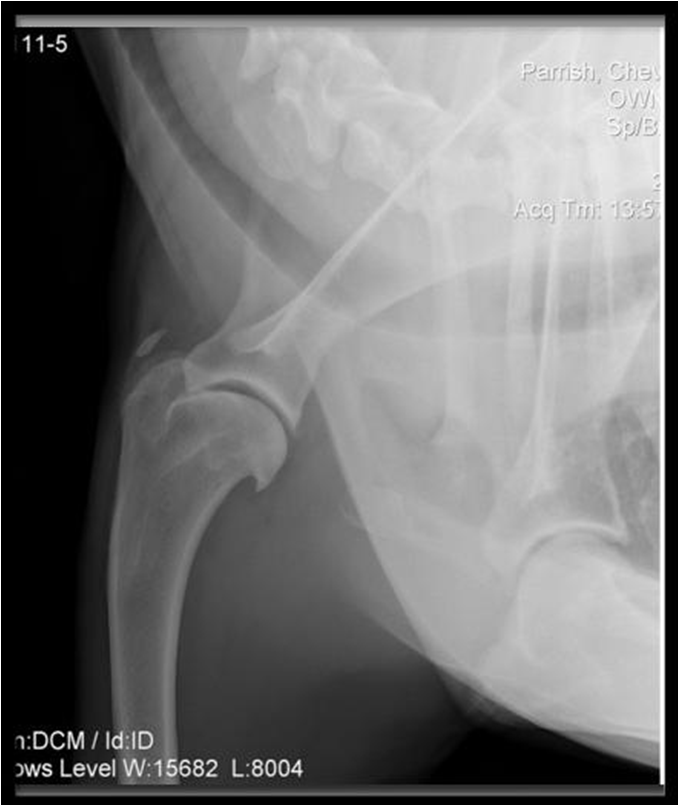

Results: Dogs aged 4 months to 14 years (average 6.5 years; median 6 years) were diagnosed with ST. Performance and sporting dogs were 39.4% of the population, with 58.1% of them being agility dogs. Pain was elicited on palpation of the supraspinatus tendon in 49.3% of dogs. Shoulder radiographs in 283 dogs showed mineralisation in 13% of cases. MRI of the shoulder was performed in 31 cases and revealed findings indicative of ST, including hyperintensity of signal on T1 weighted image (or “spin-lattice”) and Short T1 Inversion Recovery (STIR) sequences of the supraspinatus tendon at its insertion on the greater tubercle and mineralisation of the supraspinatus tendon. Common ultrasonographic findings included increased tendon size (76%), irregular fibre pattern (74%), and non-homogeneous echogenicity (92.5%). The most common findings on shoulder arthroscopy were supraspinatus bulge (82.2%) and subscapularis pathology (62.4%). Elbow pathology was recorded in 54.5% of dogs. Treatment outcomes showed 74.6% of dogs failed to respond to non-steroidal anti-inflammatory drugs (NSAID) and 40.8% failed to respond to rehabilitation.